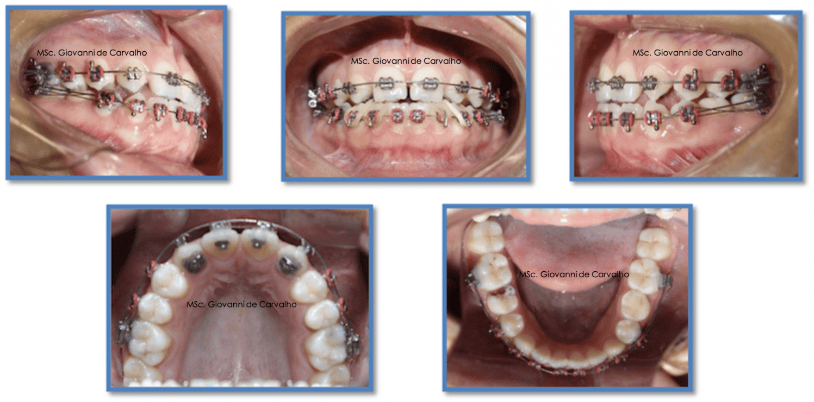

1. Aparelho superior

Instalamos o aparelho fixo na arcada superior e começamos com fios mais leves, para alinhar gradualmente os dentes. Pequenas modificações na colagem dos braquetes dos caninos ajudaram a dar uma inclinação mais natural, simulando a presença dos dentes que não existiam (os incisivos laterais).

Ainda nessa fase inicial, usamos um recurso chamado "stops" no fio, para evitar que os dentes da frente se inclinassem mais para trás e, ao contrário, os ajudassem a se projetar um pouco para frente, corrigindo a mordida.

Logo depois, iniciamos a movimentação dos dentes posteriores em direção à frente, para fechar os espaços e alinhar toda a arcada.

2. Aparelho inferior

Na arcada inferior, o aparelho foi instalado de forma convencional. Após o alinhamento inicial, removemos os dentes de leite que ainda estavam presentes e colocamos mini-implantes (pequenos parafusos de ancoragem) nos locais das extrações. Eles serviram como apoio para mover os dentes da frente para trás, corrigindo a projeção exagerada do lábio inferior.

Durante essa etapa, os elásticos intermaxilares foram fundamentais: eles ajudaram não apenas a aproximar os dentes de cima e de baixo, mas também a guiar a mordida para um encaixe correto.

3. Fase de finalização

Com a mordida corrigida, passamos para os fios mais rígidos, que dão estabilidade e permitem os ajustes finos de posição e inclinação dos dentes. O uso de elásticos de intercuspidação ajudou a deixar o encaixe da mordida ainda mais preciso.

Por fim, instalamos uma barra de contenção fixa atrás dos dentes inferiores, garantindo que o resultado fosse mantido a longo prazo.